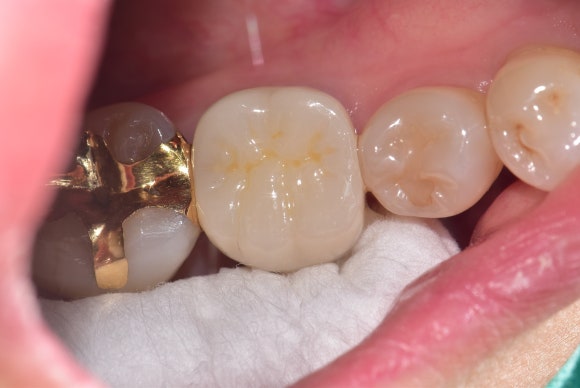

20240705

최종적으로 두 어금니 모두 건강한 상태로 확인된 후, 크라운을 이용한 최종 수복 작업을 진행했습니다.

다른 치과에서는 발치만을 권했다는 이야기를 들은 환자분은 “치아를 살릴 수 있다”는 믿음에 큰 기쁨을 감추지 못하셨습니다.